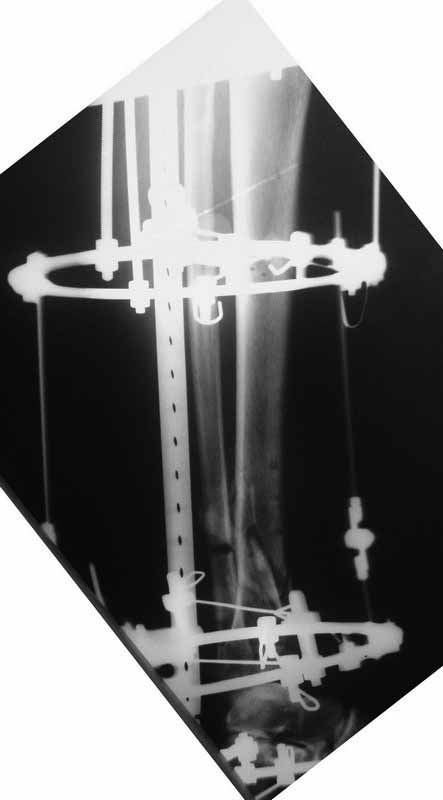

Примерная ситуация. Пациент 37 лет. Синтезировали где-то пластинкой. Попал к нам через 2 месяца.

19 апреля убрали через проколы пластину с винтами, пересекли fibula, наложили аппарат.

Немного потянули по оси, убрали вальгус, ротацию. 22 апреля (на 3-е сутки) заштифтовали окончательно. 29 апреля выписали из отделения. На все ушло 10 дней.